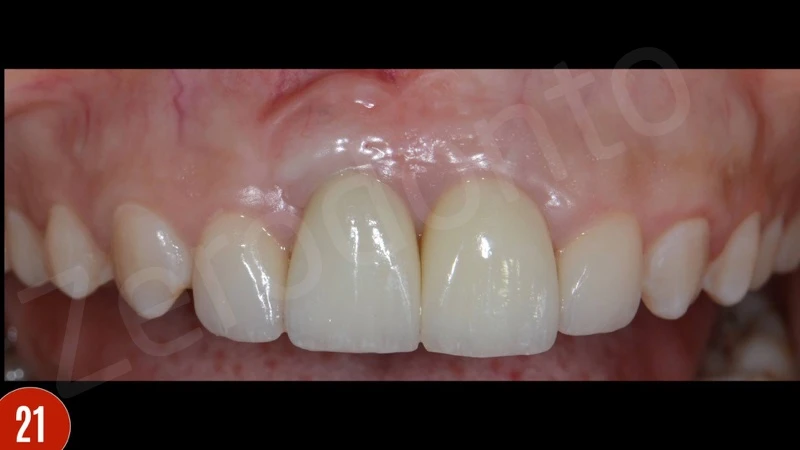

Sau 6 tháng chữa trị, phục hình tạm thời đã được gỡ bỏ và abutment tùy chỉnh được đặt. Trường hợp đã được hoàn thiện với thân răng disilicate lithium cho implant và veneers laminate cho răng cửa bên (Phục hình răng giả: Giáo sư Dr. Erhan Comlekoglu).